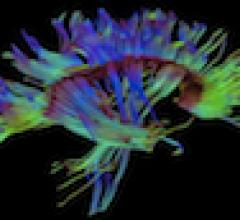

August 29, 2012 — New magnetic resonance imaging (MRI) research shows that changes in brain blood flow associated with ...

August 17, 2012 — Researchers at the Mayo Clinic say a common condition called leukoaraiosis, made up of tiny areas in ...